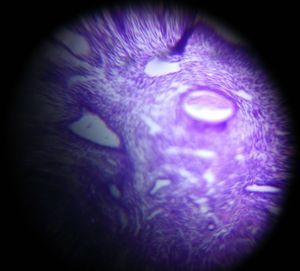

Secretory endometrium

Applause Icon140x Magnification

Secretory endometrium showing dilated endometrium glands filled with secretion